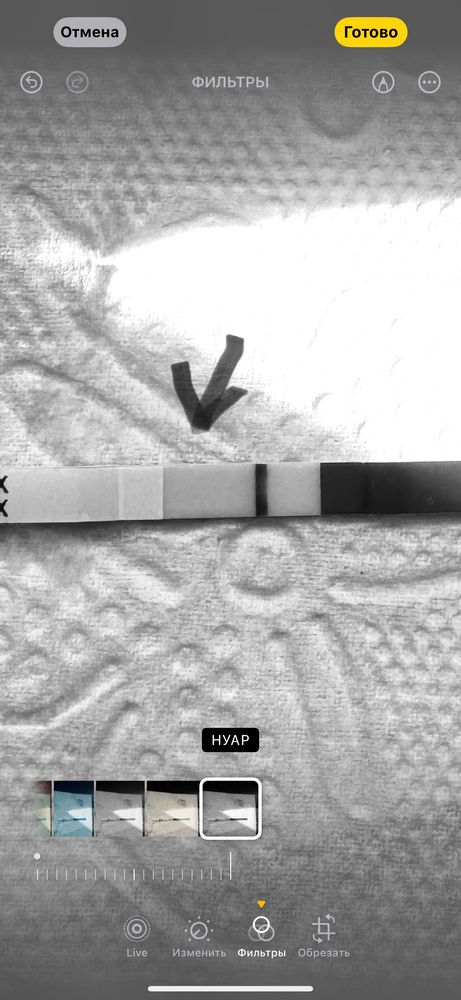

Пусто? Сделала днем

10 июля сходила на фолликулометрию нашли кисту ЖТ,ориентировочно 7-8 была овуляция ,тест днем

А вы в реале видите? Мне кажется там есть слабая полоска 🤔

Z, если серьезно в Реале нет,но я такой человек стараюсь не летать в иллюзиях , короче утром переделаю 😅спасибо за ответ